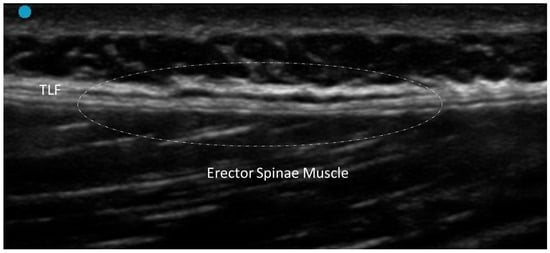

3.1. Normal Ultrasonographic Appearance of Fasciae

- Pirri, C.; Pirri, N.; Guidolin, D.; Macchi, V.; Porzionato, A.; De Caro, R.; Stecco, C. Ultrasound Imaging of Thoracolumbar Fascia Thickness: Chronic Non-Specific Lower Back Pain versus Healthy Subjects; A Sign of a “Frozen Back”? Diagnostics 2023, 13, 1436. [Google Scholar] [CrossRef] [PubMed] [PubMed Central]